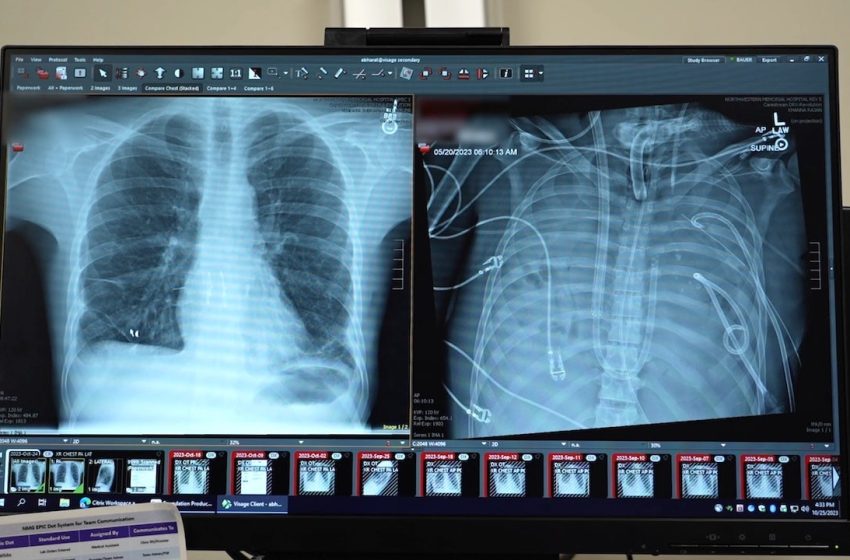

The patient’s new transplant is shown at left, and his old lungs are shown at right. “This technology allows us to ‘clean the slate’ by removing the infection, stabilizing the patient and bridging them to a successful transplant,” the lead surgeon said. (Northwestern Medicine)